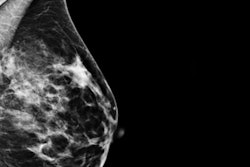

Left mediolateral oblique (MLO) digital mammography image (left) from a 49-year-old high-risk patient with extremely dense breasts. CEDM image (right) shows multiple benign rim-enhancing masses compatible with benign cysts. Images courtesy of Dr. Bhavika Patel.Real relief